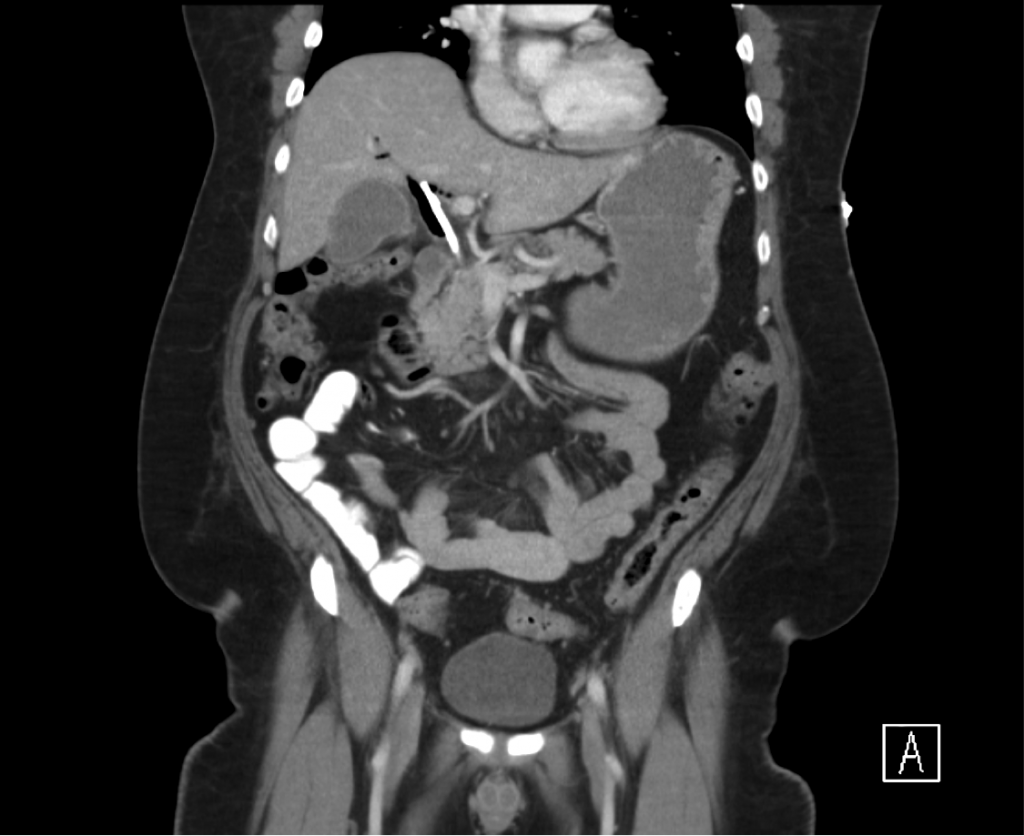

From www.wjgnet.com